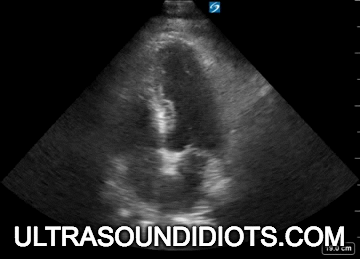

Diagnostic TRANSTHORACIC ECHOCARDIOGRAPHY

Evaluation of left ventricular systolic function

gross assessment

left ventricular squeeze - approx 50%

EPSS - should be < 5mm

MAPSE - don't measure, look for good movement